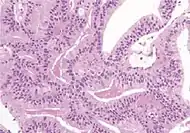

| Non acinar (or mixed acinar/ non-acinar) adenocarcinoma | Ductal adenocarcinoma | 3% to 12.7%[8][notes 1] | ![]() |

||||